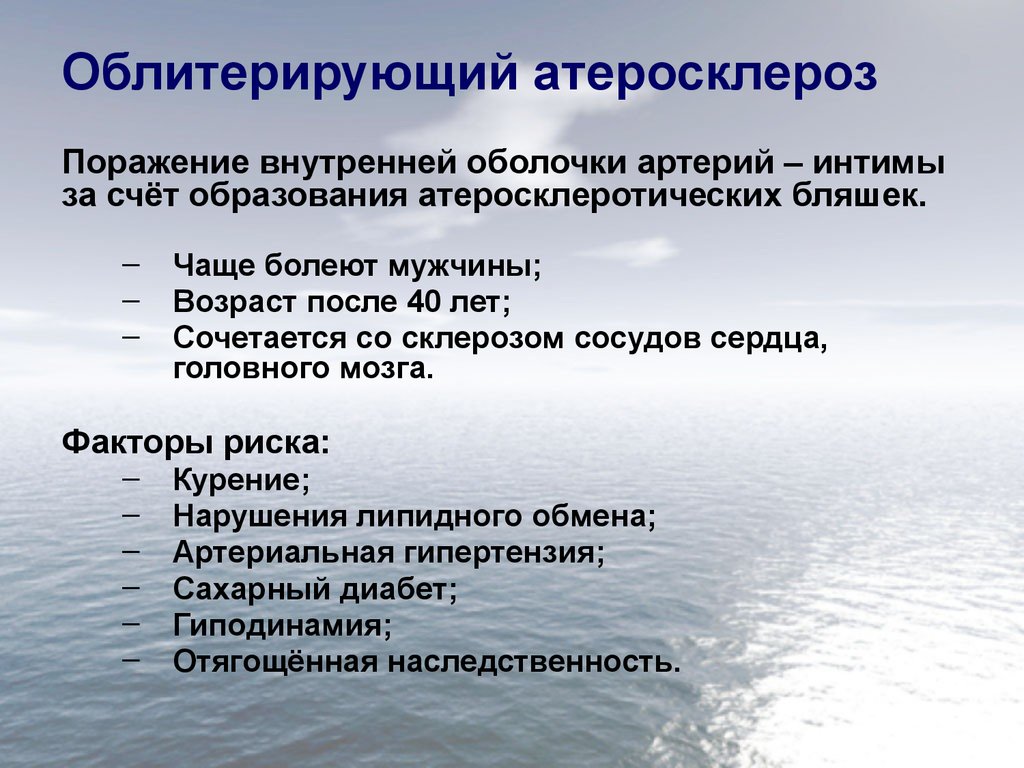

Изображения, связанные с атеросклерозом нижних конечностей и его лечением